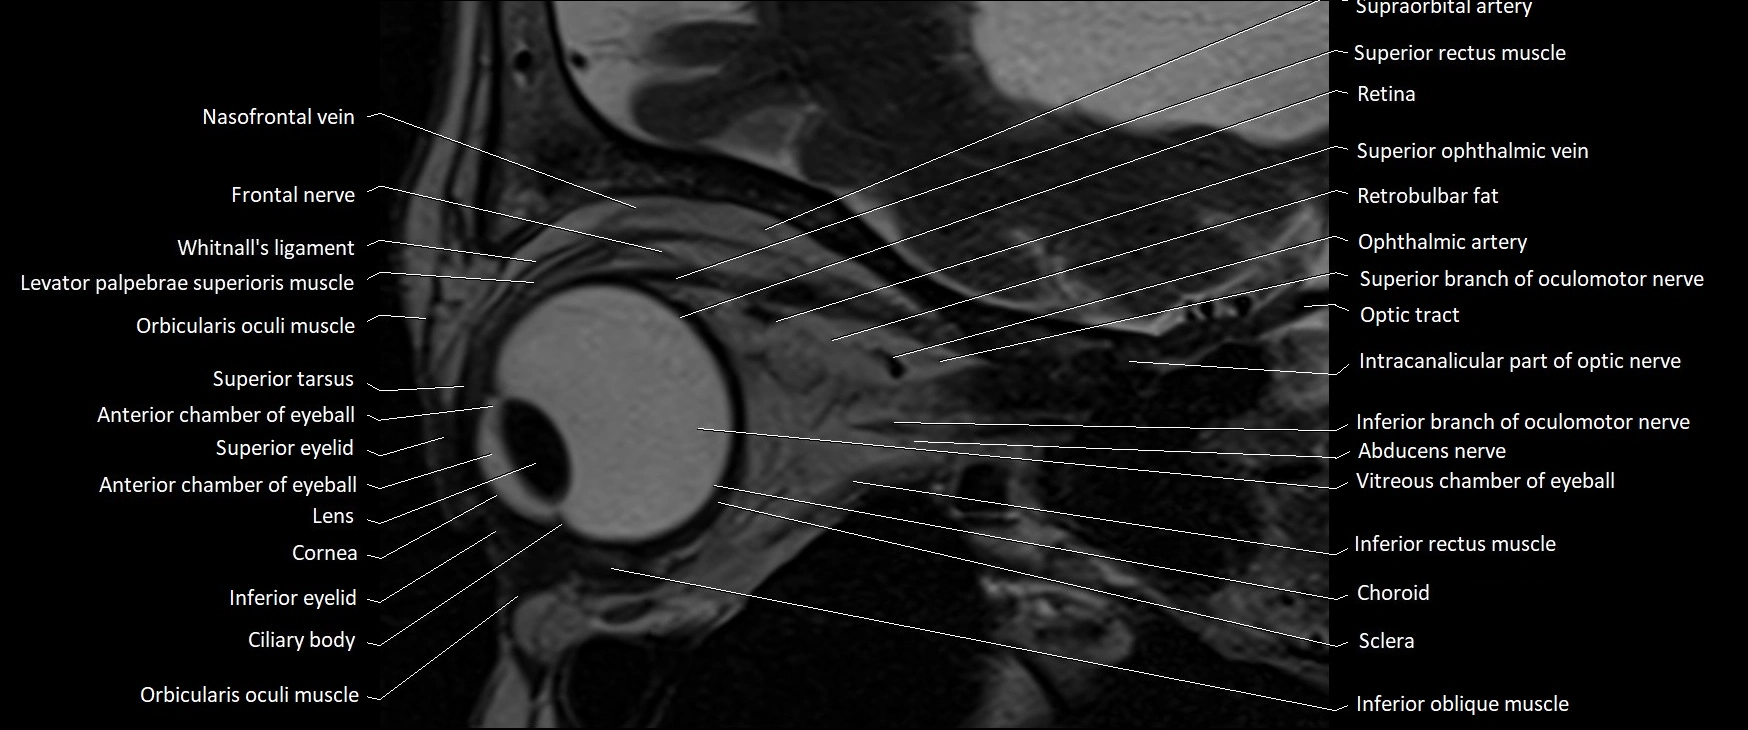

- Anterior chamber of eyeball

- Choroid

- Cornea

- Frontal nerve

- Inferior eyelid

- Inferior oblique muscle

- Inferior rectus muscle

- Intracanalicular part of optic nerve

- Levator palpebrae superioris muscle

- Nasofrontal vein

- Orbicularis oculi muscle

- Retrobulbar fat

- Superior eyelid

- Superior oblique muscle

- Superior ophthalmic vein

- Superior rectus muscle

- Superior tarsus

- Vitreous chamber of eyeball

- Whitnall's ligament

- lens of the eye